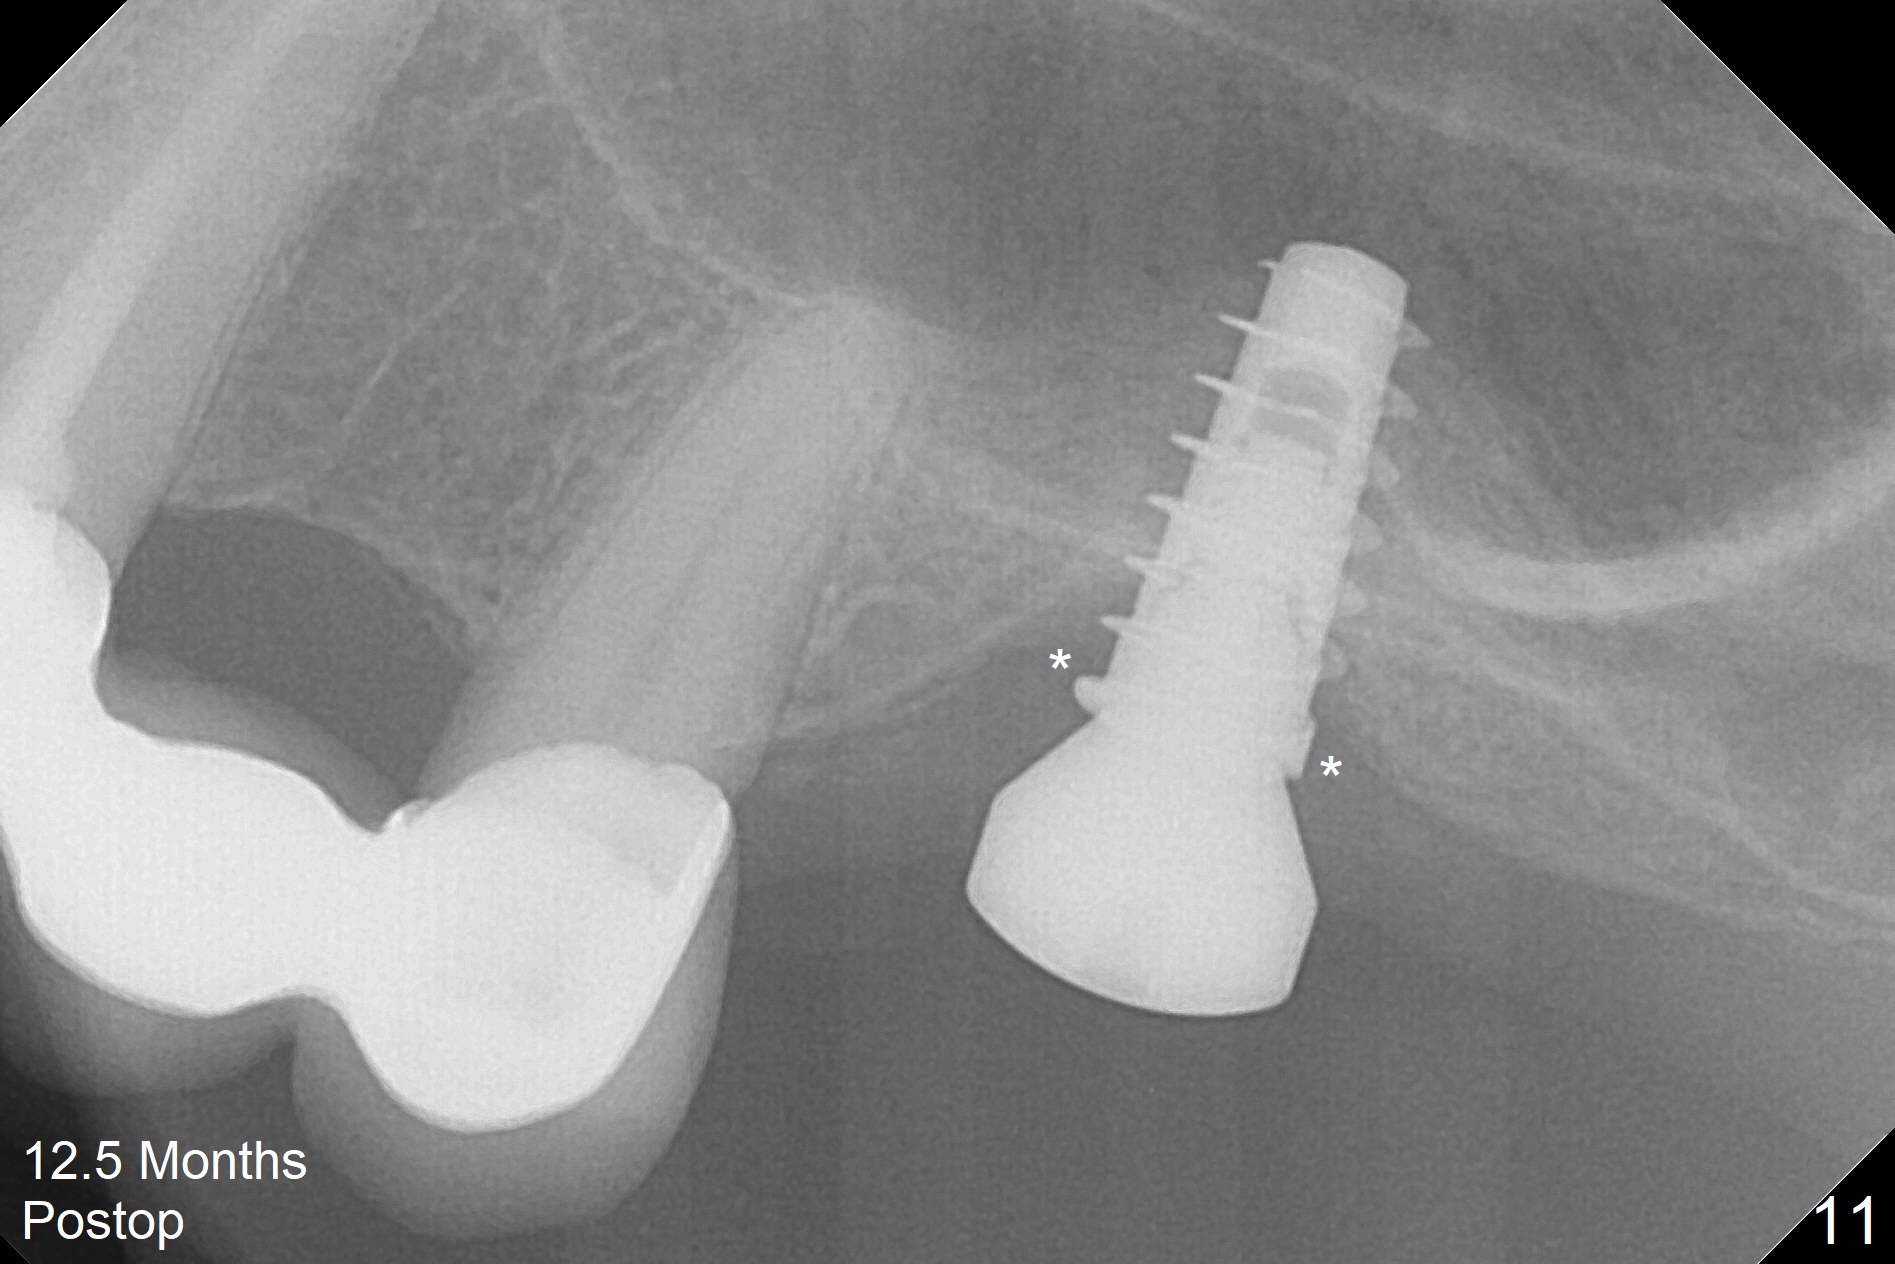

Three weeks later (approximately 8.5 months postop), the implant is found to be able to rotate when a 6.5x5.7(1) mm pair abutment is tightened with local anesthesia (there is pain associated with healing screw removal). After removal of the latter, the implant is placed deeper by hand retightening (Fig.10 arrow). Is it a better idea to use a new larger implant instead? The patient (53 years old) is scheduled to return for follow up in 3 months. In fact she returns 4 months later. The implant remains unstable and tender with loss of the crestal bone (Fig.11 *). It will be replaced with an implant (larger in diameter (5-6 mm), but shorter (7.3 mm after 5x10 mm dummy) with SLA surface after debridement and bone graft. Change the trajectory so that the coronal end will be more mesial (Fig.12 blue line). Use a healing screw and try to close the wound. In fact the patient reveals history of osteoporosis.